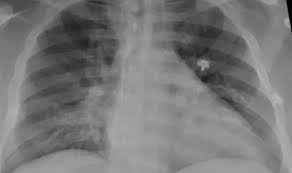

Qué es la neumonía bilateral, la enfermedad que produce más internaciones y muertes en pacientes con Cvid